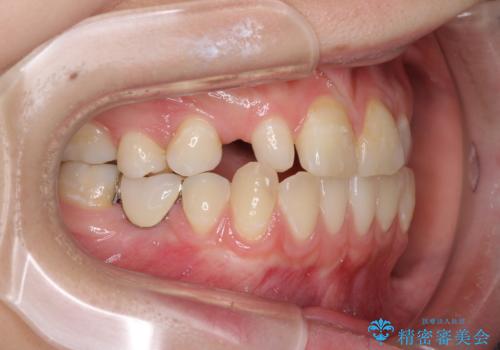

欠損と残存乳歯 矯正治療とインプラント治療

- 残存した乳歯や歯の欠損、歯並びを気にして来院された患者様です。

乳歯を残した状態は予後がよくないこと、矯正治療と補綴治療を総合的に進めていきたいとのことで、インビザラインによる矯正治療とインプラント補綴治療を並行して進めていくこととしました。

当院は矯正治療もインプラント補綴治療も、同一の歯科医師が担当するため、矯正治療を行いながら、最適なタイミングでインプラント補綴治療を行うことが可能です。